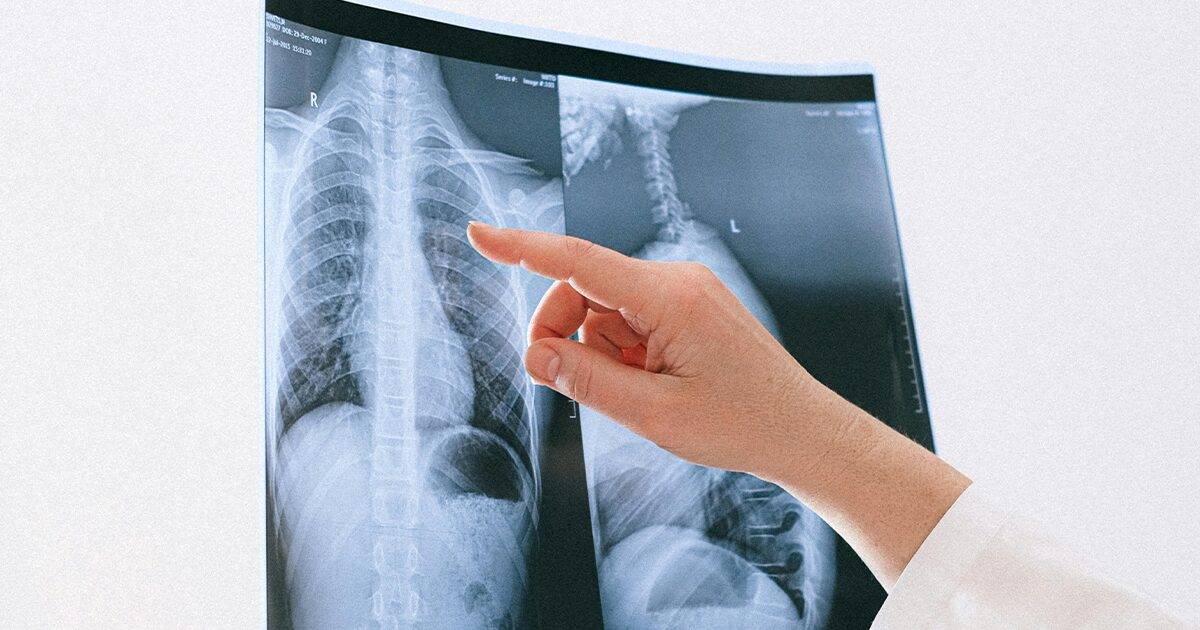

U okviru ovih izmjena, osigurana su sredstva za sufinansiranje zapošljavanja doktora medicine i stomatologije tokom 2025. godine, kao i za uvođenje novih zdravstvenih usluga, među kojima se posebno ističu skrining pluća i ABA terapija. Za svaku od ovih usluga planirano je po 100.000 KM.